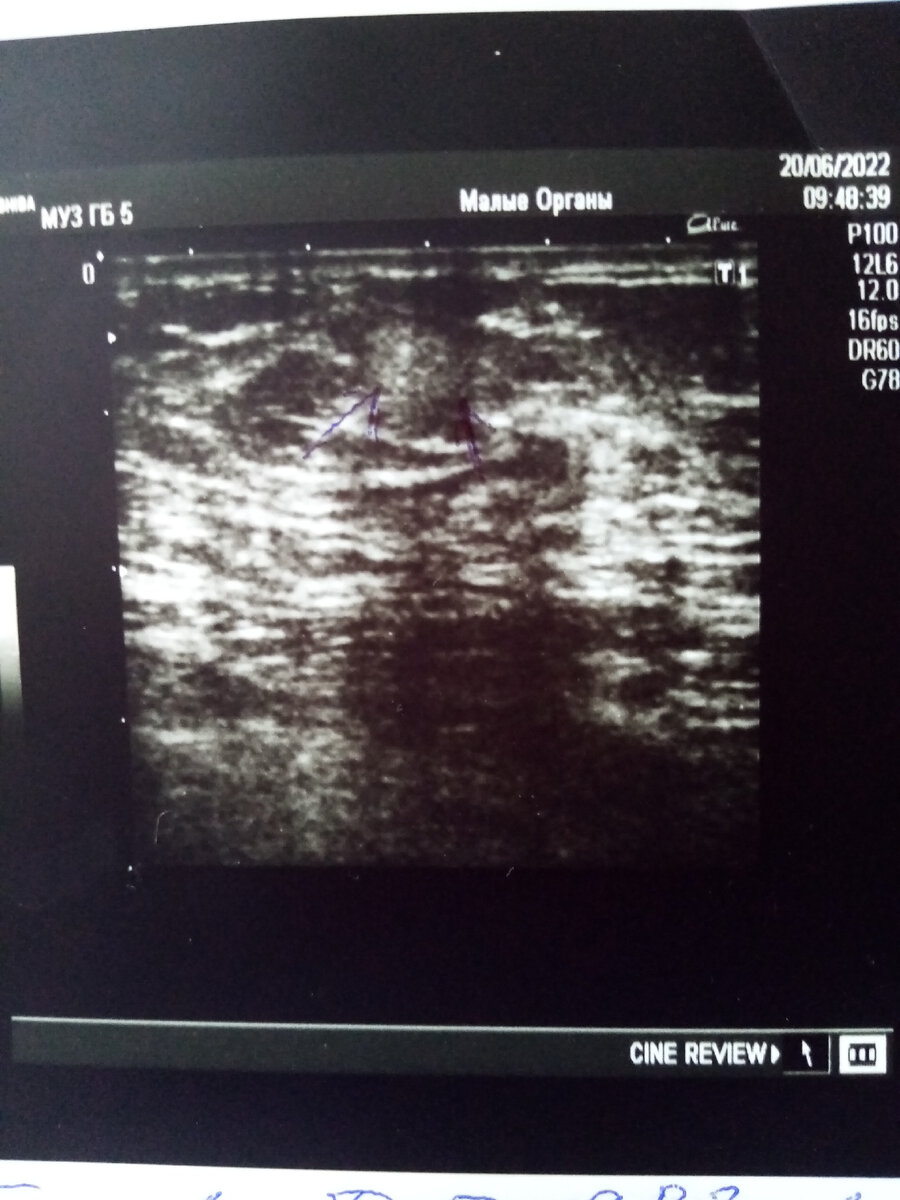

Вчера я была немного Мелманом и побежала в ЖК. Как оказалось, не зря. Мне назначили обследования и взяли анализы.